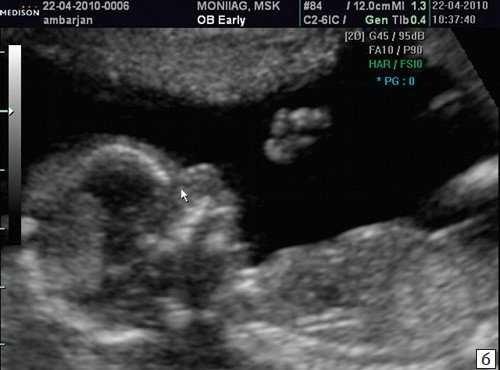

Считается, что носовая кость нормальна, когда она по своей структуре более эхогенна, чем надлежащая кожа и патологична, если она не видна (аплазия) (рис. 2) или ее длина меньше нормы (гипоплазия) (рис. 3). В случае одинаковой или меньшей эхогенности носовой кости чем кожи носовая кость считается патологической (рис. 4).

Рис. 4. Сниженная эхогенность носовой кости.